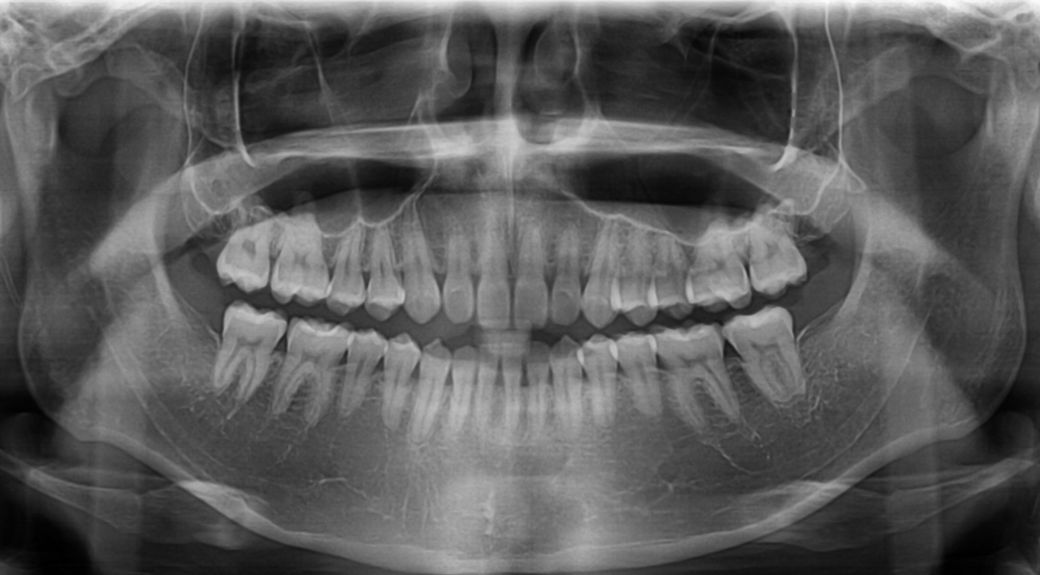

• 1번 째 사진

• 2번 째 사진

• 3번 째 사진

• 4번 째 사진

• 5번 째 사진

• 6번 째 사진

• 7번 째 사진

• 8번 째 사진

• 9번 째 사진

• 10번 째 사진

제일 위 첫번째 사진에서 윗니 1개(측절치)가 아랫니(측절치) 보다 안쪽으로 들어가 있어 정상 치아 교합이 아닙니다

왼쪽이 제1소구치쪽부터 교합이 아주 이상적인 교합은 아닙니다. 또한, 오른쪽 2번째 치아는 원래 위 치아가 아래치아를 덮어야하는데, 그렇지 않고 치아끼리 바로 닿습니다. 이 경우 치아에 무리가 갈 수 있습니다.

사진 자료만으로는 정확한 판단이 힘들며 CO, CR 등의 재현성 등을 체크해보아야할 것으로 보입니다. 물론 말씀하신 것처럼 좌우가 맞물리는 정도가 조금 다르긴 하나 대부분 사람들은 완전히 대칭을 이루기는 쉽지 않습니다. 따라서 일상생활에 불편감이 없거나 치열로 인하여 심미적으로 문제가 되지 않는 범위라면 특별히 치료를 하지 않아도 될 것으로 보입니다.